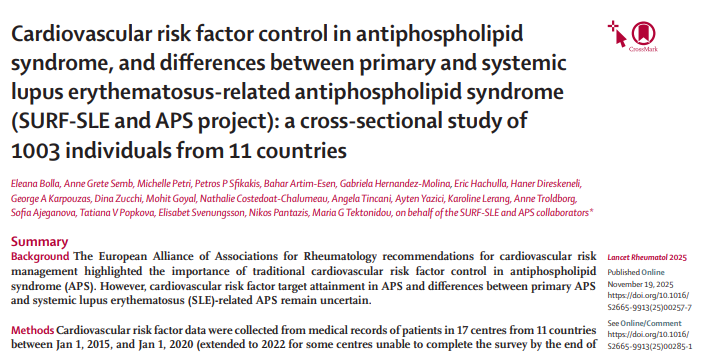

Thank you The Lancet Rheumatology for the opportunity to discuss the current evidence towards #Precision medicine in #Antiphospholipid syndrome, a rare disorder with therapeutic unmet needs.

Excited to have led this initiative and grateful for all centres' contributions to a multiethnic study of 1001 patients with #APS, underlining the need for #cardiovascular risk management in primary APS and #SLE/APS. The Lancet Rheumatology thelancet.com/journals/lanrh…